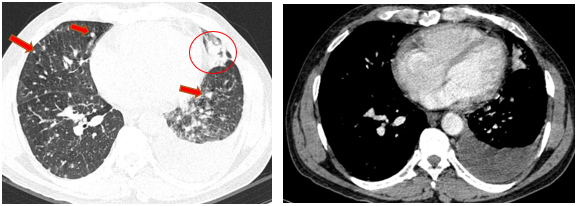

-         Chụp cắt lớp vi tính lồng ngực (08/2025): Khối rốn phổi trái ôm quanh nhánh phế quản thùy dưới trái kích thước 28x26mm, dày tổn chức kẽ vách liên tiểu thùy và nhiều nốt đặc lan tỏa khắp nhu mô, đường kính <7mm. Màng phổi trái có vài nốt đặc ngấm thuốc nốt lớn nhất kích thước 17x15mm  Khoang màng phổi trái có dịch dày 54mm. Nhiều hạch to trung thất, rốn phổi hai bên và hố thượng đòn có hoại tử trung tâm, hạch lớn nhất kích thước trục ngắn 22mm.

Hình 01: Nhiều hạch to trung thất, rốn phổi hai bên và hố thượng đòn có hoại tử trung tâm, hạch lớn nhất kích thước trục ngắn 22mm

Hình 02: Khối rốn phổi trái ôm quanh nhánh phế quản thùy dưới trái kích thước 28x26mm, dày tổn chức kẽ vách liên tiểu thùy và nhiều nốt đặc lan tỏa khắp nhu mô, đường kính <7mm.

Hình 03: Màng phổi trái có vài nốt đặc ngấm thuốc nốt lớn nhất kích thước 17x15mmKhoang màng phổi trái có dịch dày 54mm

-         Chụp cắt lớp vi tính ổ bụng (08/2025): Nhu mô gan phải có vài nốt, nốt lớn nhất hạ phân thùy VII có nốt giảm tỷ trọng, ngấm thuốc kém sau tiêm đường kính 24mm, hạ phân thùy II, III có nốt 2 giảm tỷ trọng đường kính 13mm và 27mm. Các ổ đặc xương rải rác đốt sống ngực thắt lưng, xương cùng và xương chậu hai bên – theo dõi tổn thương thứ phát